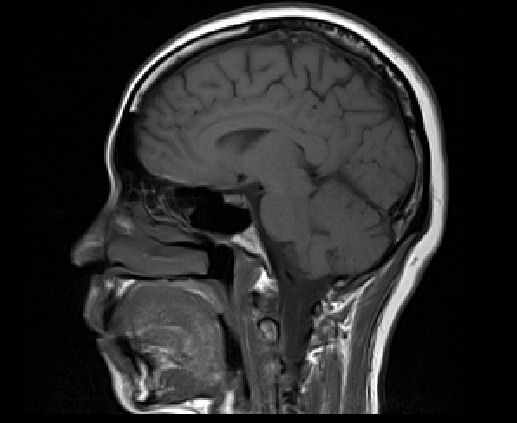

劇烈的頭痛八、九天了,不管吃任何一種止痛藥都只能暫時舒緩症狀,無法根除。白天痛,晚上也痛,尤其是右耳後方的後腦門,隨著脈搏的跳動,每天凌晨三點砰砰砰地將我痛醒。實在受不了去看醫生,他除了開處方用更強的止痛藥給我外,也讓我去做腦部磁振造影檢查 (MRI/MRA)。

做磁振造影比做電腦斷層掃描 (CT Scan) 容易多了。記得上次做電腦斷層掃描,不但要禁食,還要喝造影劑,過程中要配合技師做吸氣吐氣,也許還加上靜派注射。此次做磁振造影只是躺在那裡,頭部固定,耳中雖然有耳塞,但機器運轉的轟隆轟隆聲還是聽得到,整個過程大約三十分鐘,因為不能動,我還小睡了一下呢。

技術人員說檢查結果會直接寄給醫生,但是她可以先給我影像的 CD 。一共照了兩百多張片子,回家馬上開電腦欣賞一番,我不是醫生,當然看不出個所以然,但觀看自己腦袋內部的影像倒是蠻有趣地。現在只能靜候結果,希望一切平安無事。